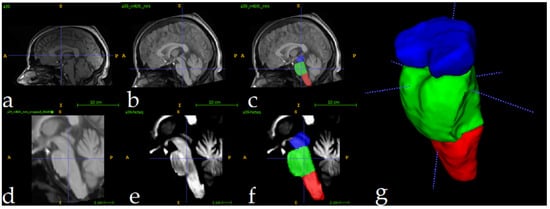

- Superior Segmentation Performance: The proposed modified U-Net architecture (with attention-enhanced skip connections and inception modules) significantly outperforms three comparative approaches in brainstem parcellation, achieving higher scores across all substructures (medulla, pons, and mesencephalon) and the whole brainstem.

- Volume Differences Across Groups: Automated segmentation reveals distinct volumetric patterns, with controls exhibiting larger volumes (whole brainstem: 1.62) compared to preclinical (1.49) and patient groups (1.12), suggesting potential atrophy linked to disease progression.

- Clinical Utility: The method’s accuracy and robustness support its potential for precise brainstem assessment in neurodegenerative disorders, enabling earlier detection of structural changes (e.g., reduced medulla volume in patients: 0.26 vs. 0.31 in controls).

| Brainstem Section | Mean Volumes (% TICV) | P | ||

|---|---|---|---|---|

| Patients | Preclinical | Controls | ||

| Mesencephalon | 0.4 | 0.44 | 0.48 | 0.007 |

| Pons | 0.47 | 0.76 | 0.82 | <0.0001 |

| Medulla | 0.26 | 0.29 | 0.31 | 0.00012 |

| Whole brainstem | 1.12 | 1.49 | 1.62 | <0.0001 |